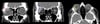

На этом изображении первый КТ-скан в корональной проекции (слева) показывает гомогенное образование, соответствующее глазному яблоку (красная стрелка). На втором КТ-скане в корональной проекции (в центре) показано образование с четкими контурами в правой ямке слезной железы (синяя стрелка). На осевом КТ-скане (справа) показано гомогенное образование слезной ямки, прилегающее к правому глазному яблоку (желтая стрелка).